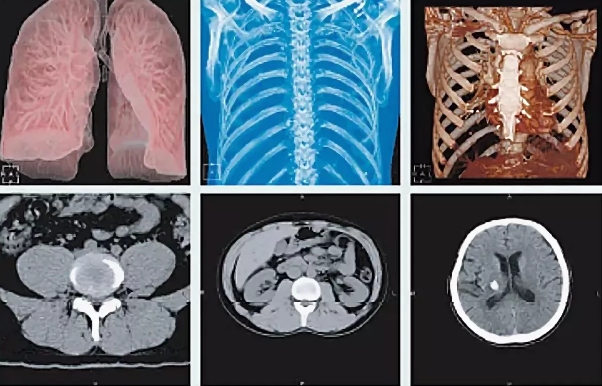

Томограф Philips Ingenuity Elite дает возможность получать высококлассную визуализацию при сниженной лучевой нагрузке в ряде педиатрических исследований, в том числе для диагностики патологии брюшной полости, легких, сосудов и костной системы в ортопедии и травматологии. В числе основных преимуществ аппарата – технология IMR, которая позволяет специалистам получать практически бесшумные изображения с существенно более низкой лучевой нагрузкой и сохранением диагностического качества визуализации. Благодаря улучшенной визуализации мелких деталей технология IMR дает уверенность в правильности полученных показателей. Массив полученных данных обрабатывается на рабочей станции IntelliSpace Portal IX, что обеспечивает высокую продуктивность работы отделения.

Четвертое поколение технологии снижения дозы iDose4 позволяет существенно снизить уровень шума на изображениях и заметно улучшить визуализацию мягких тканей и сосудов при снижении дозы на величину до 80%.Превосходные клинические возможности, ориентация на пациента, высокая рентабельность, а также низкая доза — все это Ingenuity. Никаких компромиссов.

Клинические возможности

- Увеличение пространственного разрешения при том же уровне дозы на величину до 68%

- Снижение лучевой нагрузки на величину до 50 % при увеличении пространственного разрешения на величину до 35%

- Снижение лучевой нагрузки на величину до 80% при том же диагностическом качестве изображений